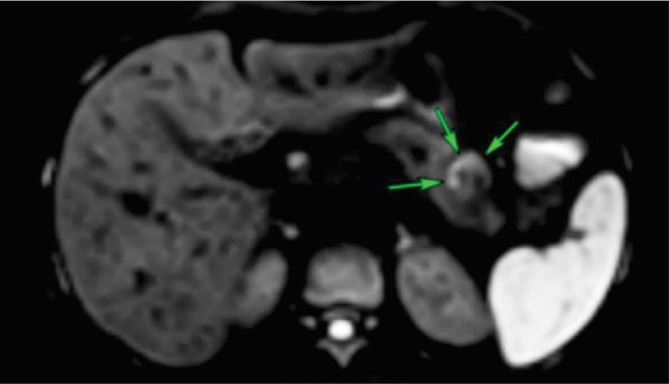

Insulinomas are rare neoplasms of the endocrine pancreas. Minimally invasive treatment options for insulinomas have gained prominence, replacing surgical resection due to its associated morbidity and mortality. Radiofrequency ablation (RFA) has emerged as a relevant treatment option. We present a case of a female patient with neuroglycopenic symptoms and severe hypoglycemic crises. The abdominal magnetic resonance imaging (MRI) showed a small nodular lesion in the pancreatic body. Laparotomy was performed, followed by RFA using a 15-mm active-tipped needle. No complications transpired, and no hypoglycemic episodes were observed during 12 months of follow-up.